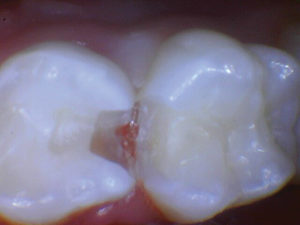

Caso 2

Un nuevo paciente de 7 años presentó una importante descomposición e hipocalcificación en el primer molar permanente superior derecho. Durante mucho tiempo se ha demostrado que los primeros molares permanentes cariados e hipocalcificados en pacientes pediátricos le dan al profesional un dilema restaurador difícil. ¿Deberíamos intentar prepararnos y restaurarlos conservadoramente? ¿Deberíamos ser más agresivos y restaurar con una cobertura completa como una corona de acero inoxidable bien adaptada? Activa proporciona una gran alternativa en estos casos, con liberación de calcio, fosfato y fluoruro junto con alta resistencia y resistencia a la fractura.

Figura 1. Después del ataque ácido y el uso del agente de unión Scotchbond Universal (3M), los dos molares primarios superiores se restauraron con Activa Bioactive Restorative A2. |

Figura 2. Una vez que se excavó la descomposición y se colocaron los márgenes en superficies sólidas, se colocó un bisel pesado en el esmalte para aumentar la resistencia de la unión y la integridad marginal. El área oscura central era sólida. El diente estaba revestido con una base / revestimiento Activa. |